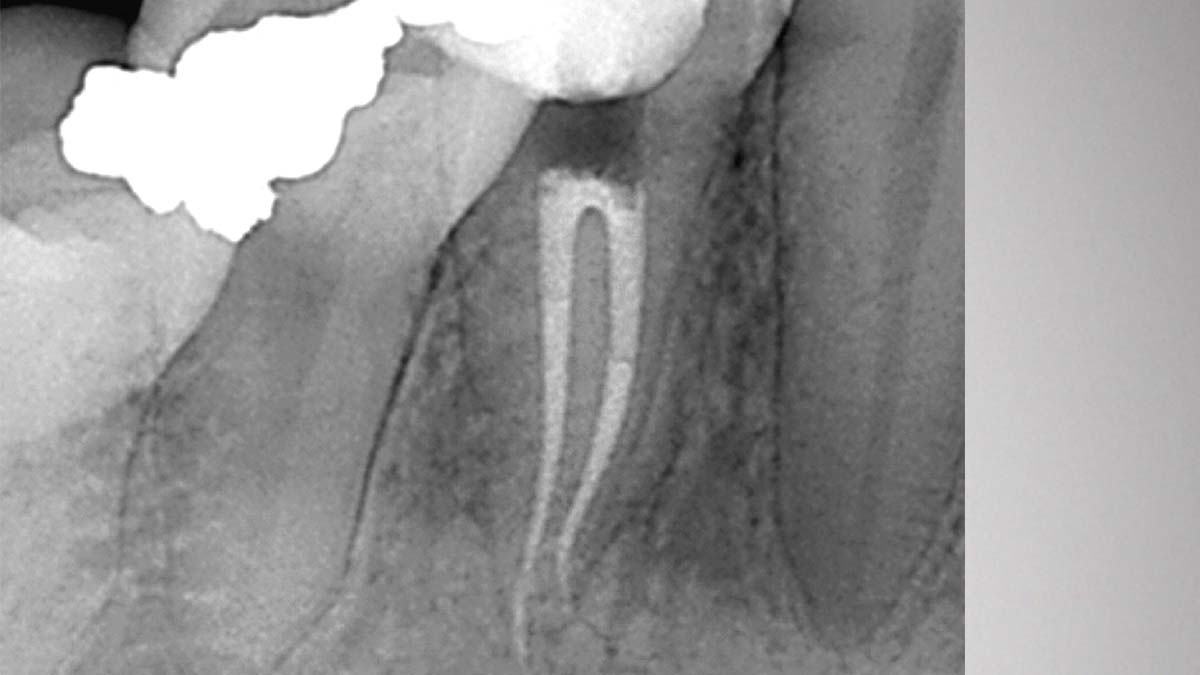

Po prawej: Gutta-Smart i Conform Fit mają tę samą zaawansowaną gutaperkę zapewniającą spójność radiograficzną.

Zdjęcie dzięki uprzejmości dr Nathaniela Behrentsa, Fayetteville, AR